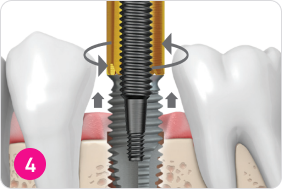

Извлечение импланта

Выберите необходимый размер инструмента для извлечения импланта. Присоедините выбранный инструмент к ключу с обратным вращением и затяните против часовой стрелки, пока он полностью не зафиксируется на импланте. Используя динамометрический ключ, приложите крутящий момент против часовой стрелки, пока имплант не начнет двигаться.